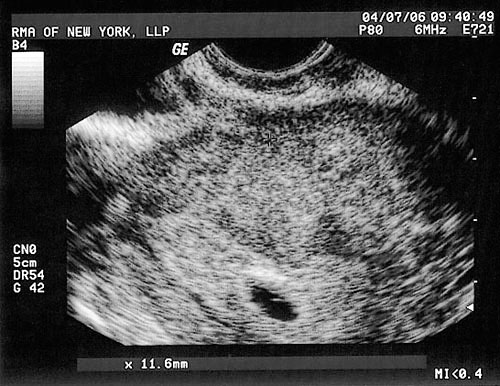

Who is that?